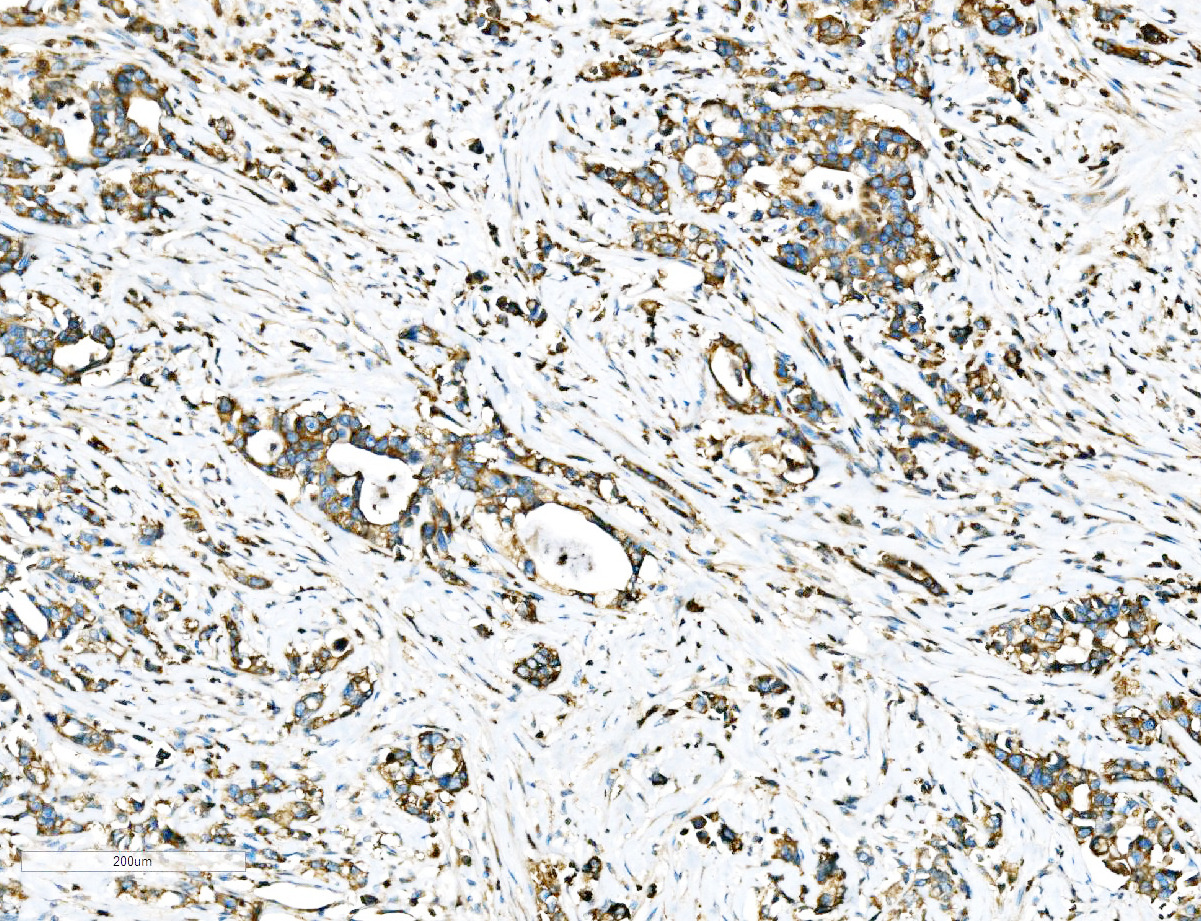

IHC analysis of Ezrin/EZR using anti-Ezrin/EZR antibody (A01750-2).

Ezrin/EZR was detected in a paraffin-embedded section of human adenocarcinoma of the right colon tissue. Biotinylated goat anti-rabbit IgG was used as secondary antibody. The tissue section was incubated with rabbit anti-Ezrin/EZR Antibody (A01750-2) at a dilution of 1:200 and developed using Strepavidin-Biotin-Complex (SABC) (Catalog # SA1022) with DAB (Catalog # AR1027) as the chromogen.